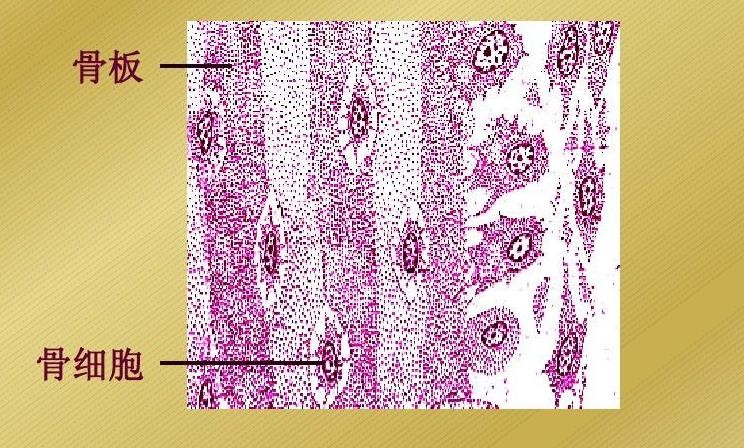

骨细胞是成骨细胞逐渐丧失成骨功能,而转变为骨细胞。多为扁椭圆形、多突起的细胞,核亦扁圆、染色深。胞质弱嗜碱性。

骨细胞夹在相邻两层骨板间或分散排列于骨板内。相邻骨细胞的突起之间有缝隙连接。在骨基质中,骨细胞胞体所占据的椭圆形小腔,称为骨陷窝(bone lacuna),其突起所在的空间称骨小管(bone canaliculi)。相邻的骨陷窝借骨小管彼此通连。骨陷窝和骨小管内均含有组织液,可营养骨细胞和排出代谢产物。